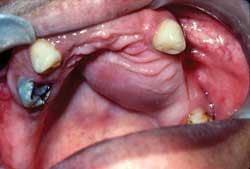

Perioral and intraoral characteristics: Clinically, the pleomorphic adenoma will manifest as a slow–growing, painless, mobile mass when found in the lower lobe of the parotid gland. Swelling in the area of the angle of the mandible may be noticed clinically by the patient. The tumor may also be found in the palate and in this location, the growth appears as a bulbous, nonulcerated, firm lesion.